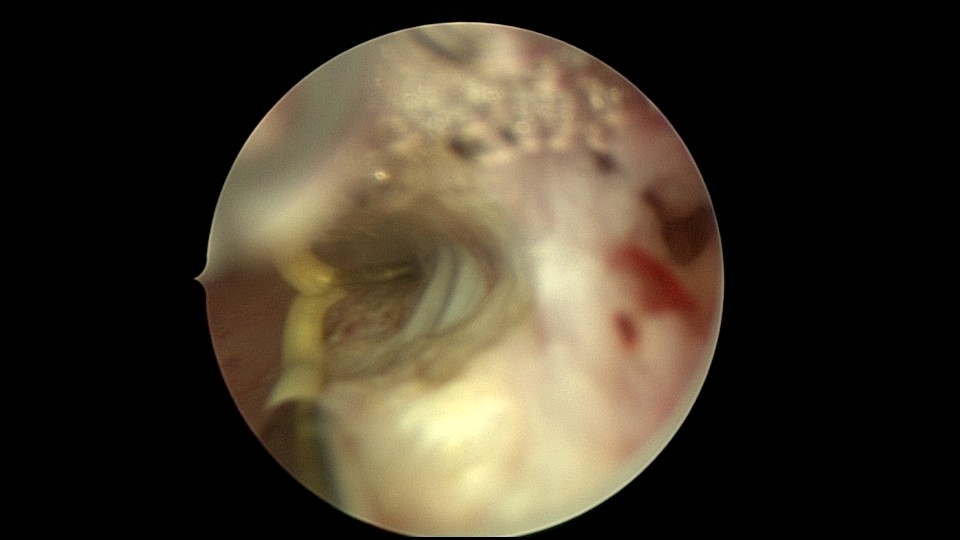

患者26岁,G7P1,剖宫产1次。2019年10月药流不全,行清宫术,术后闭经半年,后月经紊乱,周期28天~60天,月经量少。2021年4月,闭经50+天,B超提示宫腔粘连,宫腔镜见宫颈管上段封闭粘连,宫腔广泛粘连,AFS评12分(最高分)。宫腔镜电切分粘,恢复宫腔形态,显露双侧输卵管开口,宫腔防粘连复发处理,2021年5月宫腔镜二探取球囊。2021年7月自然妊娠,门诊人流并安环。2021年9月,月经推迟,B超提示宫腔粘连,节育环嵌顿,行宫腔镜取环并分粘,2021年10月二探取球囊。2021年12月放置皮埋避孕,2022年3月要求取出皮埋棒。2023年8月初自然妊娠,药流不全,2023年8月底行宫腔镜清除残留胚物。2024年2月自然妊娠10周,2024年4月初妊娠3+月(BPD2.6cm),坚决要求终止妊娠,行宫腔镜辅助终止妊娠。2025年6月因异常子宫出血再次宫腔镜分粘,2025年7月二探取球囊。现31岁,G10P1,前后共做了8次宫腔镜,术后多次自然妊娠,患者妊娠中途均选择了终止妊娠。